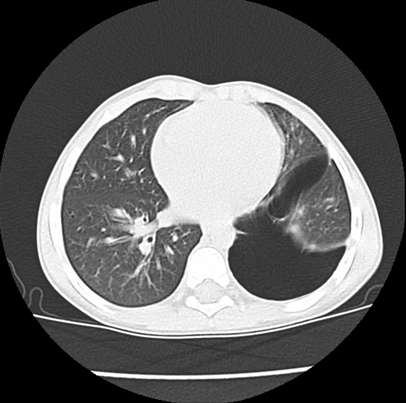

We asked for a Chest CT scan